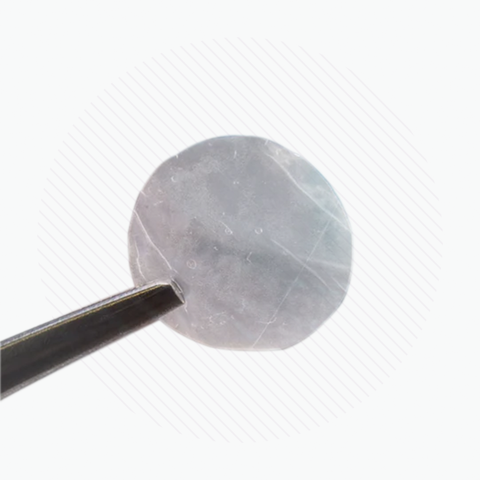

• Textured surface facilitates ease of handling and placement

• Symmetric graft allows either side to be placed in contact with ocular surface

• Can be placed in either direction (multi-directional graft)

• Has a micron thickness of 30-35 Microns

Apply either graft surface to the wound site; Symmetric design removes stromal layer/epithelial layer facing requirements

Graft may be manipulated in place and/or repositioned during surgery